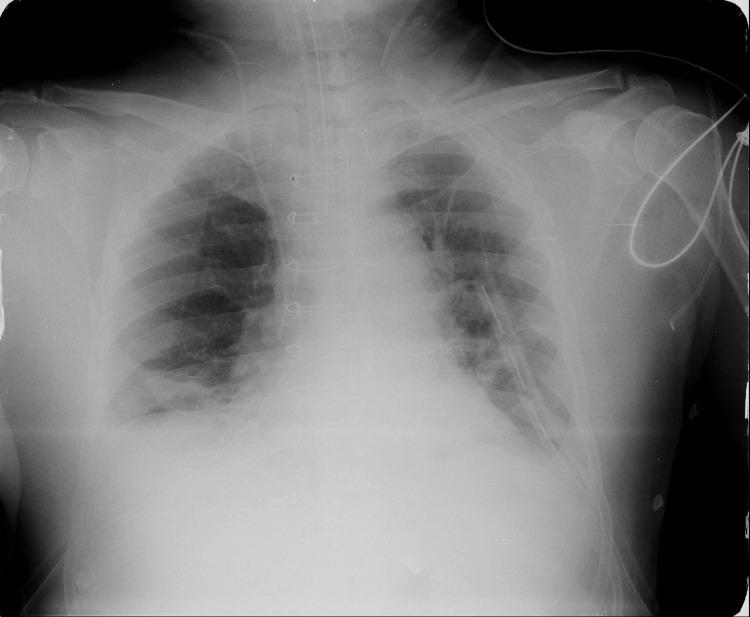

Sternal wire displacement is a rare but important postoperative complication following median sternotomy, commonly performed during cardiothoracic surgeries, such as coronary artery bypass grafting (CABG). While wire breakage and migration are known, migration into the deep subcutaneous plane without involvement of intravascular or muscular structures is extremely uncommon. We report a 71-year-old male with a history of triple vessel disease status post CABG 12 years prior, presenting with acute dyspnea. Imaging revealed pulmonary edema and an incidental finding of a migrated sternal wire in the deep subcutaneous plane anterior to the pectoralis major. Serial chest X-rays demonstrated gradual disruption and migration of the lowermost sternal wire over several years. The patient remains asymptomatic regarding the wire migration and is being managed conservatively with regular follow-up. This case highlights an unusual presentation of sternal wire migration confined to the subcutaneous plane, emphasizing the importance of long-term radiological surveillance in post-sternotomy patients. Although often asymptomatic, displaced sternal wires may pose significant risks, necessitating individualized management strategies. Conservative monitoring with periodic imaging is a reasonable approach when the patient is asymptomatic and the wire is stable.

https://cdn.ncbi.nlm.nih.gov/pmc/blobs/2903/12460196/00b182b10fd5/cureus-0017-00000090915-i01.jpg